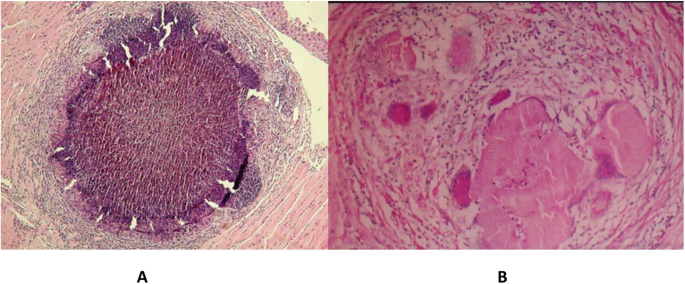

A Two fragments of Actinomadura pelliterii grain surrounded by multiple neutrophils (Type I reaction). Stained with H&E X40. B Actinomadura madurae grain. Note the variegated pattern and fragmentation. The periphery of the grain is dense, homogeneous, and deep purple, while the centre is less dense and even appears hollow. Stained with H&E X40.

The ultrastructure of the grain is quite distinctive. The hyphae are septate, compact without cement substance, and under low magnification, they have a starry sky appearance because of the vacuoles in the hyphae. These are probably fixation artefacts. Neutrophils adhere to the grain, degranulate, and phagocytose grain material, which is then destroyed, and this process is frequently observed63.

Actinomadura madurae grains

Macroscopically, the grains are yellow or white. They are difficult to distinguish from the surrounding fat92. Histologically, the large grains have a characteristic variegated pattern. The periphery of the grain is dense, homogeneous, and deep purple, while the centre is less dense and even appears hollow. Not infrequently, the grain fragments into geometric fragments. The periphery shows a brightly eosinophilic material forming clubs. This material contains immunoglobulins. Smaller grains are more homogeneous and are difficult to distinguish from Actinomadura pelletierii. However, even the small grains of Actinomadura madurae have a more deeply stained purple fringe, which is not seen in Actinomadura pelletierii. The inflammatory reaction is similar to that of Actinomadura pelletierii63,91 (Fig. 8B).